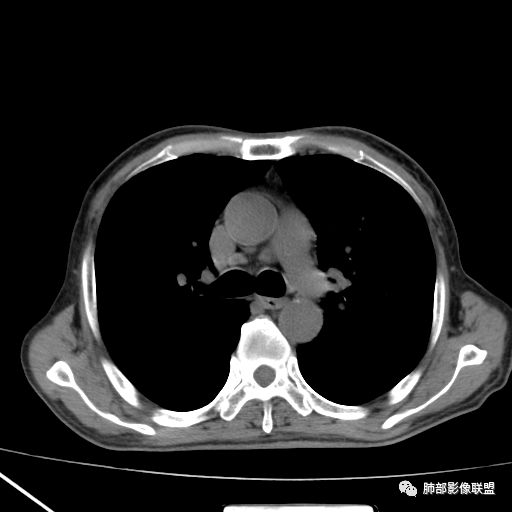

2019.08.24:胸部CT增强扫描:左肺上叶纵膈旁软组织结节影,双肺弥漫性小结节及细网状影,纵膈淋巴结肿大,心包积液,肝左叶散在低密度影。(没见片子)

现病史:患者于2个月前无明显诱因出现咳痰、咳痰,咳白粘痰或黄痰,有时痰中带血,伴发热,最高体温40.5度,多于下午起热,伴乏力盗汗,有时恶心呕吐,先后至日照市中心医院及青岛大学附属医院住院治疗,给予哌拉西林钠他唑巴坦及拜复乐抗炎,氟康唑抗真菌及对症支持治疗,患者入院检查痰培养(2019-09-08青岛大学附属医院)肺炎克雷伯菌。骨髓穿刺(2019-09-10青岛大学附属医院)检出1.5%异常浆细胞,胞浆kappa单克隆阳性。胸部CT(2019-08-24青岛大学附属医院)左肺上叶软组织影,双肺弥漫小结节并细网状影,纵膈淋巴结肿大,心包积液。自发病来,饮食睡眠差,体重较前下降约15斤。

10月20日的CT其实是抗痨治疗近1月复查的CT。患者来我院后抗痨治疗体温下降,症状明显好转。